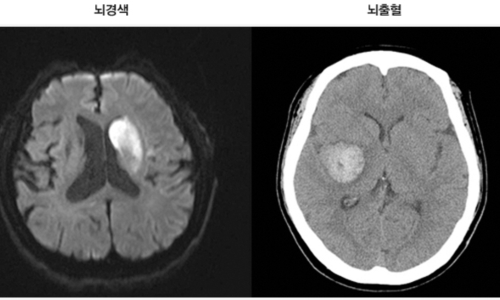

뇌혈관이 막히거나 터지는 질환을 통칭하는 것이 뇌졸중이고 그 중 뇌혈관이 막히는 것이 뇌경색 그리고 뇌혈관이 터지는것을 뇌출혈이라고 합니다. 뇌졸중은 영구적인 손상이 많고 증상에 따라 전신이나 신체 일부 기능이 마비되는 등의 심각한 후유증이 남는 무서운 질병인데요 오늘은 뇌경색 초기증상 및 뇌경색 치료방법에 대해 알려드리겠습니다.

신체가 건강해도 뇌에 문제가 생기게 되면 신체 기능을 제대로 할 수가 없게 됩니다. 뇌 손상으로 제한된 신체 기능은 치료를 마친 후에도 회복이 제대로 되지 않거나 장애로 남는 경우가 많은데 뇌조직이 괴사되며 발생하게 되는 뇌경색이 대표적입니다. 과거에는 뇌출혈 환자가 많았지만 현재는 전체 뇌졸중 환자의 약 60~70%가 뇌경색 환자인 만큼 뇌졸중에서도 뇌경색이 차지하는 비중이 크다고 합니다.